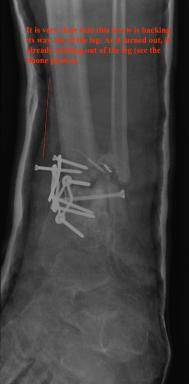

Post-infection X-Rays of the damaged right & left legs / ankles

After the last surgery Liam developed Staphylococcal (staph) infection as well as Osteomyelitis on the bone. Liam went to the ER of

Tempe St. Luke with a temperature of over 104 degrees and severe pain of the left leg. Liam was released from the ER with a diagnosis of

Gastroenteritis and instructions to follow up with a visit to Dr. Armendariz. Four days later and with a continued very high temp, Liam was

seen by Dr. Armendariz. Dr. Armendariz immediately performed 3 surgeries to clean out the infected areas of both the left and right leg and

to place wound vacs on the damaged areas of the legs.

An interesting point to note, as it applies to the second and third x-rays (from the left), is the placement of the last screw at the bottom

of the right legs fibula plate. Notice how Dr. Keller completely missed the plate. Not only is the screw useless, but it has started protruding

in such a way as to cause severe pain and require padding to keep from bursting through the skin. A later surgery is planed for the screws

removal.